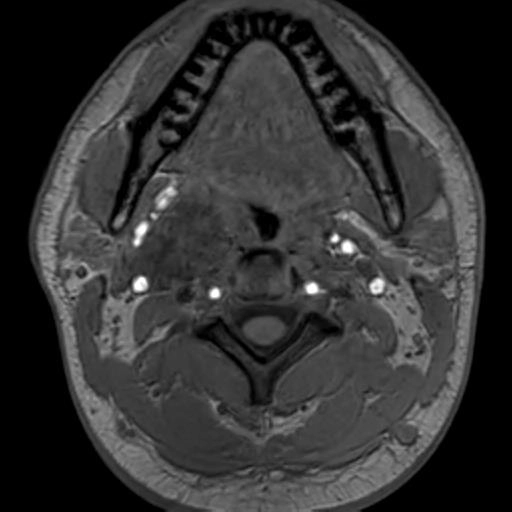

U thể cảnh/ u cận hạch thể cảnh (Carotid Body Paraganglioma)